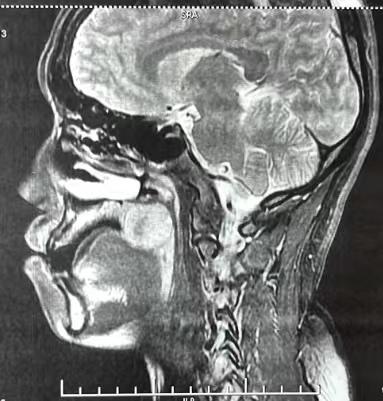

患者王女士(化名)一年前发现右侧腭部隐匿的小肿物,初期未加重视。谁料肿瘤突然生长加速,导致吞咽困难。患者来到徐州市口腔医院,经仔细检查,确诊为"右侧腭部-口咽部交界区巨大肿瘤"。

术前

咽旁间隙被医学界称为"手术雷区",其邻近血管、神经等重要结构,风险较大。面对挑战,医院迅速集结口腔颌面外科、麻醉科精锐力量,经过三次多学科会诊,量身定制了"三维定位+精准剥离"的手术方案,并预设了完善的应急保障体系。

术前检查